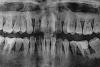

teberda Опубликовано 2 февраля, 2013 Поделиться Опубликовано 2 февраля, 2013 Здравствуйте! Проконсультируете пожалуйста. Вот два снимка, сделанные с разницей в год. Врач рекомендовал срочно делать кюретаж, лоскутную операцию всех зубов, шинирование (пломбирование"шнурком" всех зубов с внутренней стороны как сказал врач). Но не дает гарантии. Мне 26 лет, детей нет. Изучаю сейчас сайты, форумы. Очень мучает вопрос почему это случилось, дело в том, что была большой фанаткой зеленого чая, и где-то недавно прочитала, что он очень негативно влияет на зубы, не уже ли из-за этого? Возможно ли этот процесс остановить каким-либо образом кроме операции? На сколько плачевная ситуация? Как срочно стоит делать операцию? Или Имплантация? Ссылка на комментарий

Solnyshko Опубликовано 2 февраля, 2013 Поделиться Опубликовано 2 февраля, 2013 Здравствуйте! Проконсультируете пожалуйста. Вот два снимка, сделанные с разницей в год. Врач рекомендовал срочно делать кюретаж, лоскутную операцию всех зубов, шинирование (пломбирование"шнурком" всех зубов с внутренней стороны как сказал врач). Но не дает гарантии. Мне 26 лет, детей нет. Изучаю сейчас сайты, форумы. Очень мучает вопрос почему это случилось, дело в том, что была большой фанаткой зеленого чая, и где-то недавно прочитала, что он очень негативно влияет на зубы, не уже ли из-за этого? Возможно ли этот процесс остановить каким-либо образом кроме операции? На сколько плачевная ситуация? Как срочно стоит делать операцию? Или Имплантация? Гарантии ,действительно ,здесь никто не даст.Мысль про чай отбросьте. Провериться нужно у эндокринолога,все ли в порядке со щитовидной железой? диабет? у кардиолога,гастроэнтеролога? Есть ли аутоиммунные заболевания? Наследственность? Постараться выявить причину. Должна быть идеальная гигиена,купить ирригатор, профгигиена не реже раза в полгода. Посев из карманов на микрофлору,может антибиотики придется пропить. И ,конечно лоскутные.. Ссылка на комментарий

Bier Опубликовано 3 февраля, 2013 Поделиться Опубликовано 3 февраля, 2013 Ситуация очень плачевная. Надо думать не то, что об операции, которую надо было делать еще вчера, тут впору подумать о тотальной имплантации.Но прежде общее обследование. Ссылка на комментарий

IvanK Опубликовано 4 февраля, 2013 Поделиться Опубликовано 4 февраля, 2013 +1Обследование.Лоскутные операции + фанатичное отношение к гигиене, в случае, если планируется съемное протезирование. Шинирование сильно усугубит гигиену, что приведет к более быстрой потере менее подвижных зубов...Если есть возможность задумайтесь о тотальной имплантации. Ссылка на комментарий